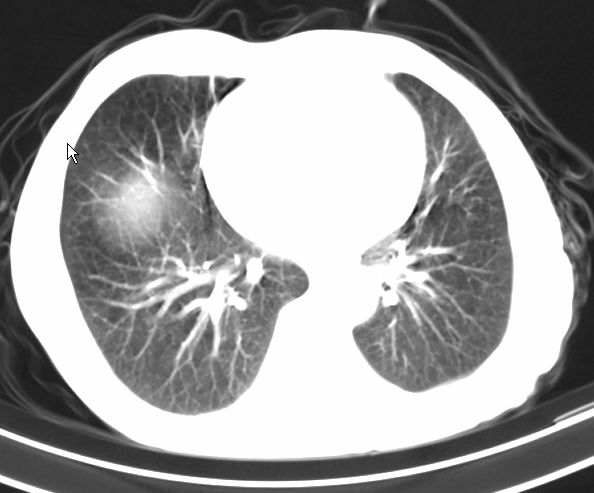

请大家看看是什么性质的。炎性病变首先考虑哪一种炎症。

支持右肺上叶前段\\下叶内基底段感染,建议抗炎治疗后复查,除外结核.

支持右肺上叶前段、下叶内基底段感染,建议抗炎治疗后复查,除外结核.

右肺上叶前段及下叶内基底段感染性病变;建议抗炎治疗后复查。

楼主说是炎症,凭啥?典型的周围型肺癌(腺癌可能性大),肝内可能已有转移,强化看看吧。